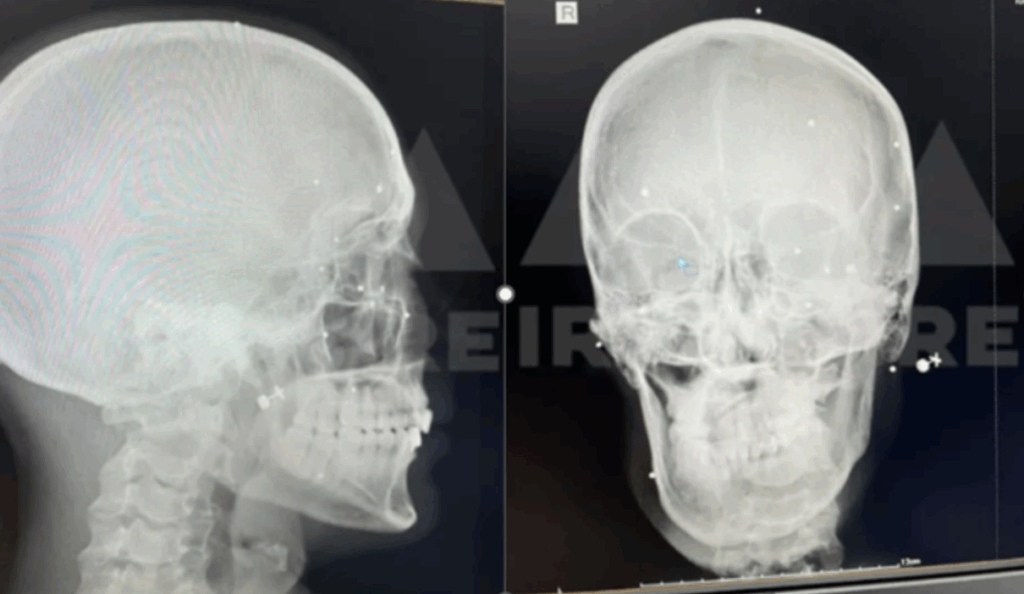

To prepare this report, the medical files of a number of individuals with eye injuries were shared with a global group of ophthalmology specialists. The results of their evaluations show that the pattern of eye injuries points to deliberate targeting. According to these specialists, the trauma caused by blindness is psychologically comparable to the experience of being diagnosed with cancer. This conclusion underscores the profound physical and psychological damages inflicted by this suppression tactic.

Furthermore, dozens of interviews were conducted with individuals injured during the protests, several of which are referenced in this report. Medical evidence was reviewed to corroborate the types of munitions used. Interviews with six physicians—including ophthalmologists and emergency medicine specialists in Tehran who had examined the gunshot wounds sustained by protestors—provided key insights regarding weapon type, shooting distance, and targeting practices. In addition, dozens of medical records from injured individuals were analyzed to assess the severity, nature, and location of their injuries. These findings were further reinforced by a specialized report prepared by IranWire in collaboration with health researcher Katherine Hignett, who reviewed and analyzed the medical files of 20 individuals affected during the 2022 protest suppression.[6]

Medical records of numerous victims who were shot in the head and eyes with shotgun projectiles demonstrate that the ammunition was discharged at close range. One such case is that of Hossein, a middle-aged man who lost both eyes and was permanently blinded. His medical file documents the presence of at least 300 pellets embedded around his eyes. At the time, he and his wife were attending the 40th-day memorial ceremony for Hadis Najafi, a young protester, in Karaj in Alborz Province. Witness accounts and medical evidence indicate that Hossein was shot with a shotgun while lying motionless on the ground as an act of submission.[94] Out of fear of reprisals by the Iranian government, he has chosen to remain anonymous.